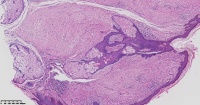

纤维瘤?

性别

女

年龄

22岁

临床诊断

一般病史

右侧面部丘疹10年

标本名称

面部包块

大体所见